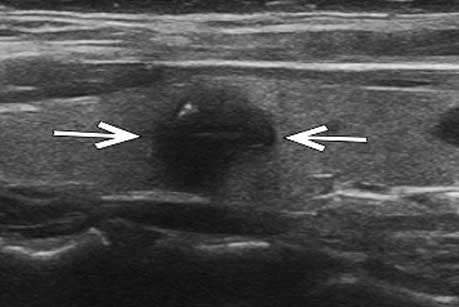

甲状腺左叶实性结节,形态欠不规则,边界尚清,局部紧邻后方被膜,结节内部可见强回声钙

超声造影全程结节无增强